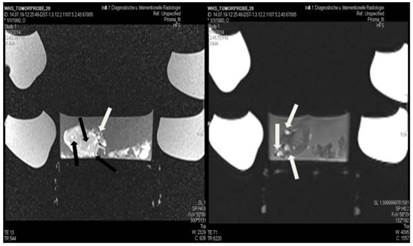

Figure 10

Lipiodol, cisplatin and microwave group; T1 sequence: Heterogeneous appearance with hypodensity sites indicating necrosis. T2 sequence: Heterogeneous appearance with hyperdensity sites indicating necrosis with hemorrhage around the spike wound. White formations are lipiodol molecules entrapped within the tumor tissue (white arrows).

Tumor necrosis and apoptosis were the major purposes of our study. Survival was also recorded. Our records and MRI findings indicate that a major toxicity was observed in the group where cisplatin, lipiodol and microwave were applied. None of the animals survived more than a week. Moreover; hemorrhage apart from necrosis was observed inside the tumors. Survival was the following for the groups: microwave (25days) ≥ cisplatin (22 days) > control (20 days) > lipiodol (16 days)> microwave plus lipiodol (16 days) > cisplatin plus lipiodol (12) > cisplatin plus microwave (12 days) > lipiodol plus cisplatin plus microwave (5 days). (Figure 5-12.)